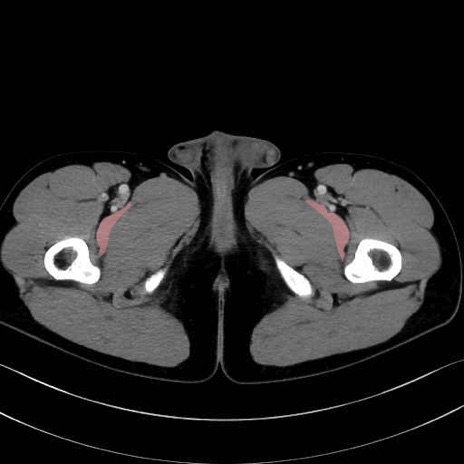

恥骨筋 (Pectineus)